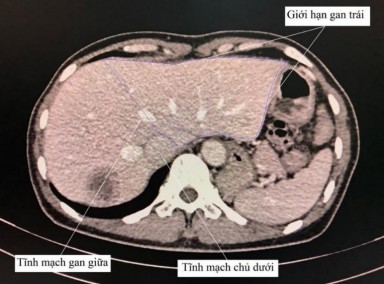

- Xác định các mốc giải phẫu gan trên phim chụp X quang cắt lớp vi tính/cộng hưởng từ: tĩnh mạch chủ dưới, tĩnh mạch gan phải, giữa và trái, tĩnh mạch cửa phải và trái.

- Xác định tĩnh mạch gan giữa và tĩnh mạch chủ dưới trên phim X quang cắt lớp vi tính hoặc cộng hưởng từ.

- Đo diện tích riêng phần của gan trái trên từng lát cắt: giới hạn bên phải là đường thẳng nối từ tĩnh mạch gan giữa đến tĩnh mạch chủ dưới, giới hạn còn lại là chu vi gan trái.

- Thể tích gan trái chính là tổng toàn bộ các thể tích riêng phần đo được tại từng lát cắt tính được nhờ phần mềm cài đặt trên máy tính.

Hình 2.3. Cách xác định ranh giới gan trái khi đánh giá thể tích gan (Nguồn: Bệnh viện Đại học Y Dược TP.HCM)